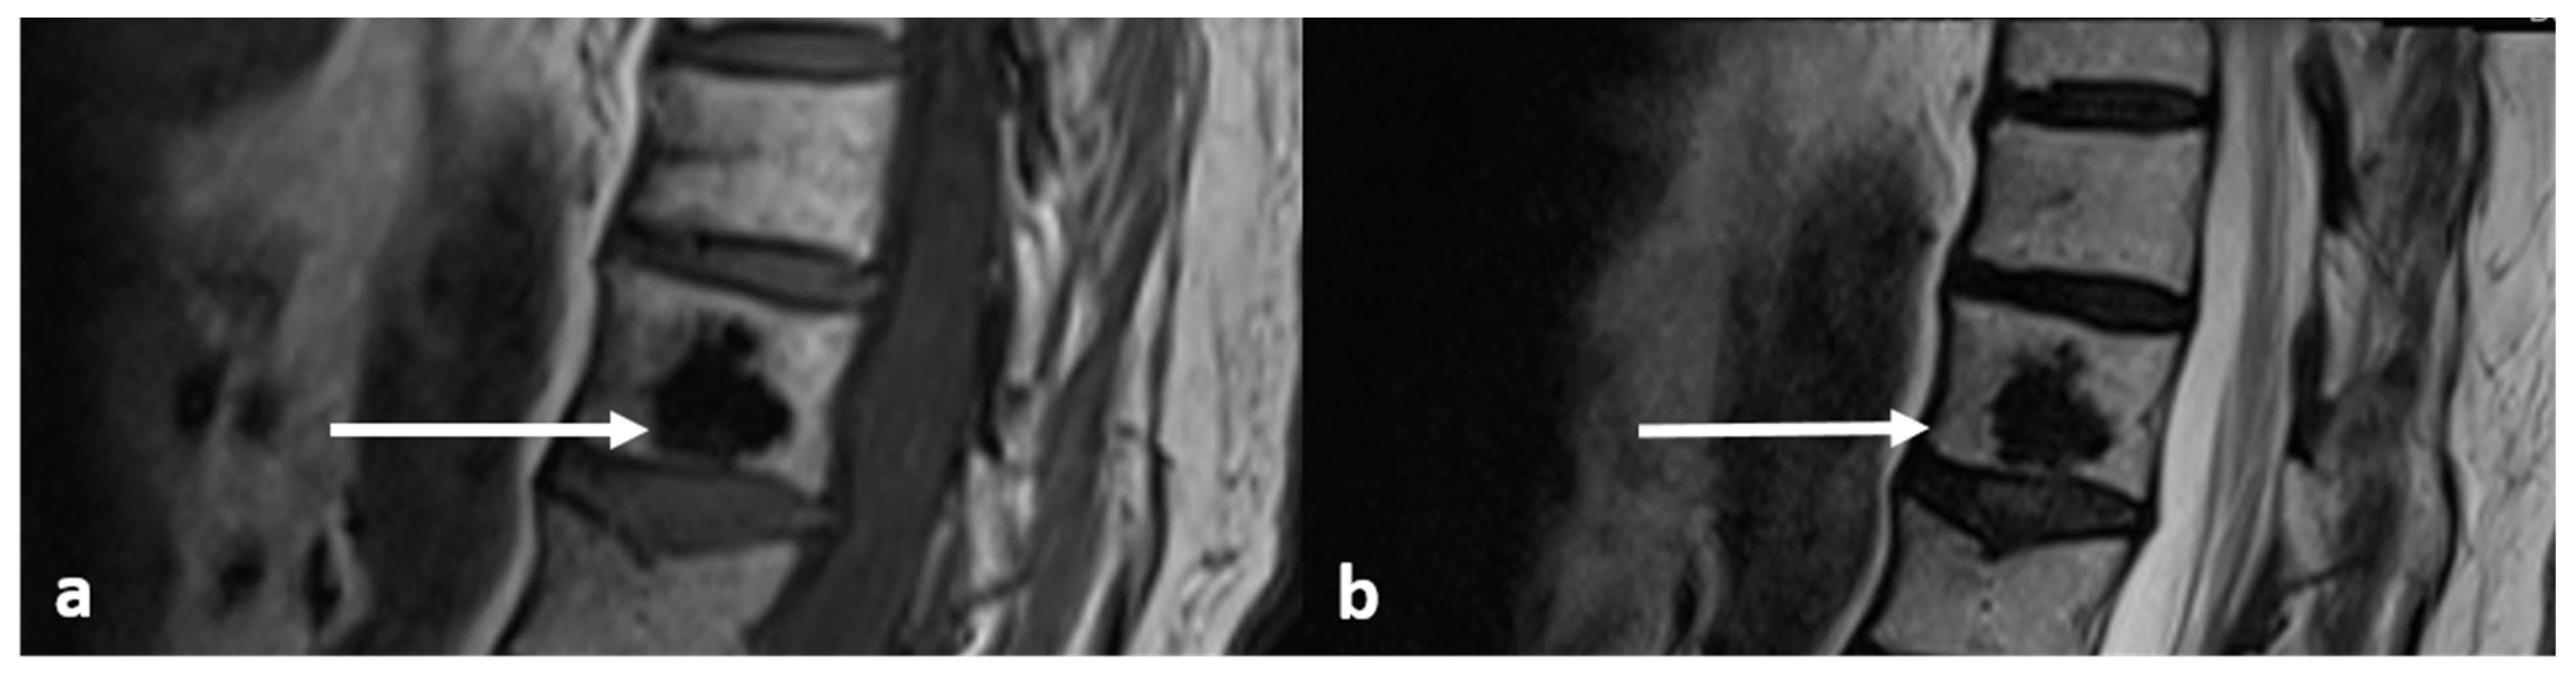

| Osteoid osteoma | Lucent nidus, usually 2–10 mm. May be surrounded by sclerotic rim. | Surrounding marrow oedema on fluid sensitive sequences (best seen on STIR). Nidus can be occult on MRI. |